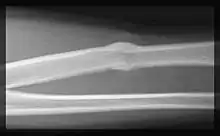

Formação de um calo ósseo após um fratura.

Calo ósseo é uma formação de osso na área de uma fratura óssea enquanto que o osso tenta regenerar-se.[1] A nível celular, envolve a formação de fibroblastos e condroblastos.[2]